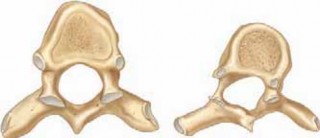

Chapter 57 Segmental Hook and Pedicle Screw Instrumentation for Scoliosis James T. Guille and Reginald S. Fay…

Chapter 56 Posterior Exposure of the Thoracic and Lumbar Spine James T. Guille and Reginald S. Fayssoux DEFIN…